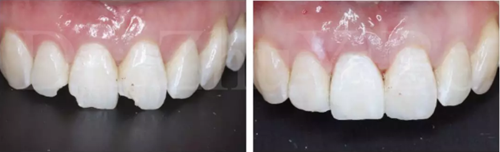

圖16 即刻修復后,患者恢復了美觀

即刻種植&即刻修復屬于高技術敏感性的操作,一旦出現(xiàn)美學并發(fā)癥往往很難處理,所以,要做好美學區(qū)即刻種植一定要從術前設計、病例選擇入手,全面考慮影響即刻種植美學效果的關鍵因素,在掌握好必備的知識與技能后,再嘗試即刻種植的治療。